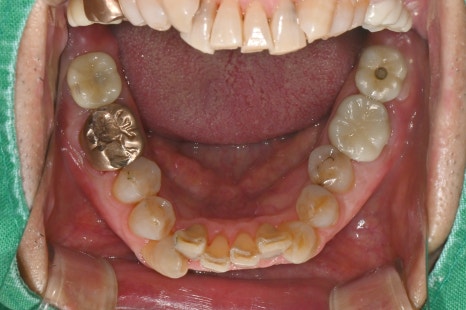

📸 환자 치료 전·후 사진

왼쪽 사진: 임플란트에 메웠던 레진이 떨어져 구멍이 그대로 드러난 모습입니다. 음식물 끼임의 위험이 있어 빠른 치료가 필요했습니다.

오른쪽 사진: 탈락된 부분에 레진을 다시 채워 깔끔하게 마무리한 모습입니다.

자연치아와 조화롭게 복구되었고, 통증이나 불편함 없이 사용 가능합니다.